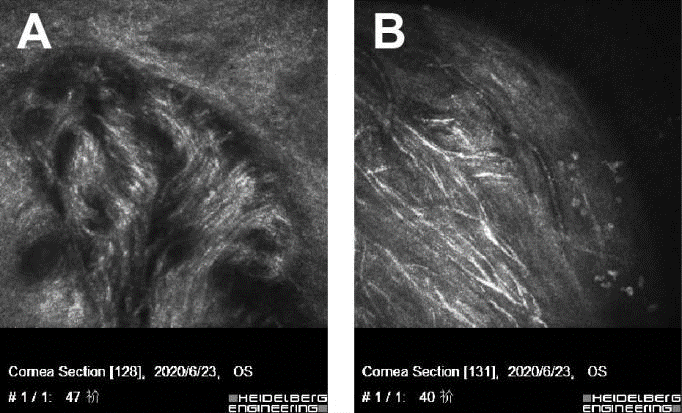

In vivo confocal microscopy (IVCM) is a non-invasive method used to assess the living corneal nerve morphology in both physiological and pathological states. IVCM was performed on the cornea with the Heidelberg retinal tomograph Ⅲ Rostock cornea module. Corneal IVCM images of the patient revealed a normal endothelium, with a sparse hyperreflective and thickened nerve plexus in both eyes (Figure 3). IVCM images of neuromas showed a disorganized bundle of nerves composed of elementary hyperreflective nerves with bifurcations, loops, and dilations (Figure 4).

Figure 3. In vivo confocal microscopic images of cornea. No obvious abnormalities were found in the corneal pterygoid cells and basal cells. A, corneal sparse subbasal nerve plexus. B, hypertrophic nerves in anterior stroma. C, A few thin nerve fibers forming loops and showing nodular dilatations. Thickened main corneal nerve trunk appearing as a bright, hyperreflective structure, Penetrating and bifurcating here. D, highly reflective hypertrophic nerves with bifurcations in midstroma, about 80μm in diameter. E, thin nerve fibers present in posterior stroma. F, normal endothelium.